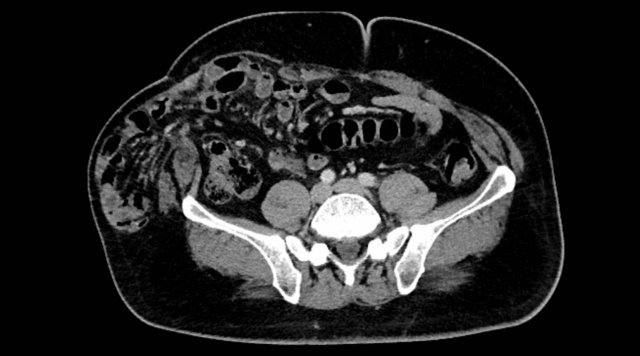

Peritoneal Carcinomatosis